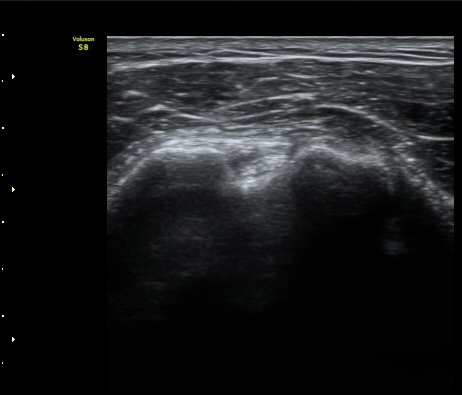

À̵ιڱ٠Ⱦ´Ü¸é°Ë»ç¿¡¼­ Á¡¾×³¶³» °í¿¡ÄÚ ¼®È¸È­ À½¿µµéÀÌ °üÂûµÊ(±×¸² 1, 2, 5)

À̵ιڱ٠Á¾´Ü¸é°Ë»ç¿¡¼­µµ Á¡¾×³¶³» ¼®È­È­ À½¿µÀÌ °üÂûµÊ(±×¸² 4).

ÁÖ»ç ÈíÀΰú Á¡¾×³¶³» ÁÖ»çÄ¡·á(÷ºÎ ÆÄÀÏ) 1ÀÏ ÈÄ ½ÃÇàÇÑ °Ë»ç¿¡¼­ Á¡¾×³¶ÀÇ ºÎÁ¾ ¹× ¼®È¸ÀÇ

Á¦°Å°¡ °üÂû µÊ(±×¸² 6, 7).